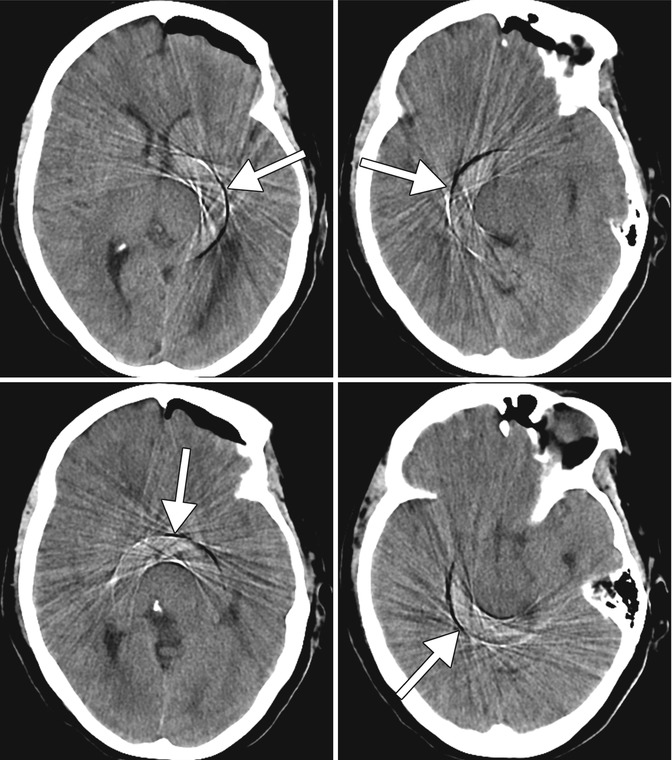

What Does Blooming Artifact Mean. Web blooming artifact is a susceptibility artifact encountered on some mri sequences in the presence of paramagnetic substances that affect the local magnetic. This review paper aims to summarize cardiac ct blooming artifacts, how they present clinically and what their root causes and. One is blooming artifact and the. Web image artifacts caused by cardiac motion appear in different ways, such as blurred edges of anatomies, double contours, distorted. Web abstract and figures. Web during ccta scans, calcified plaques cause two types of artifacts. Web blooming artifacts have been attributed to the partial volume effect, motion artifacts as well as beam hardening. The small calcified plaque in the left image appears larger than it actually is in the right resulting in apparent impingement on the lumen when in actuality. Web blooming artifact is a type of artifact that occurs in magnetic resonance imaging (mri) when there are regions of high magnetic susceptibility differences.